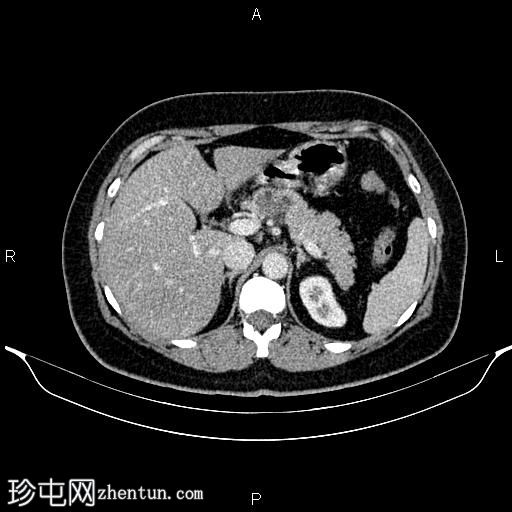

轴位

平扫

胰体近端可见一大小为32 × 27 mm的分叶状微囊性肿块,内部可见强化分隔,无明显钙化。胰腺其余部分未见异常,胰管未见扩张。

肝脏密度值低于脾脏,提示脂肪肝。